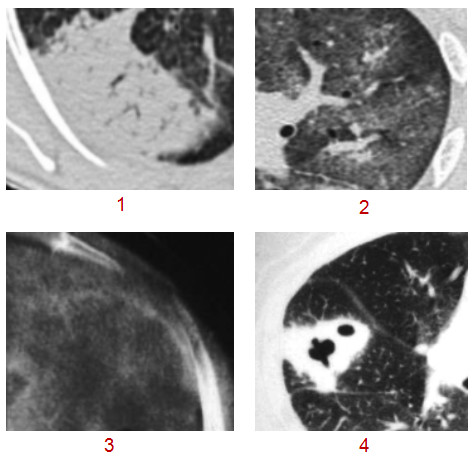

病变的形态包括大叶(段)性阴影、小叶性阴影、腺泡状阴影、小叶中心阴影、类球形阴影(晕征、反晕征)、不规则状等。

1 中叶大片的大叶性阴影、2 小叶性阴影、3 腺泡状阴影、4 类球形阴影 5 小叶中心结节及晕征 6 不规则改变

1 中叶大片的大叶性阴影、2 小叶性阴影、3 腺泡状阴影、4 类球形阴影 5 小叶中心结节及晕征 6 不规则改变